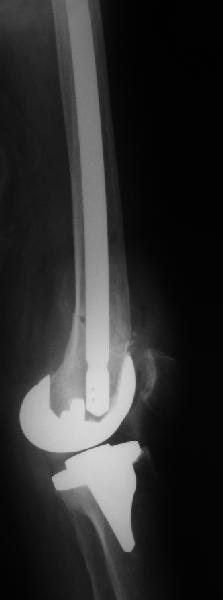

То, что планируется - наиболее распространенный подход. Еще менее инвазивный вариант - закрытый антеградный интрамедуллярный остесинтез. Мы используем гвозди, которые выпускаются предприятием ЦИТО, т.е. недорогие. Там в дистальное отверстие можно ввести 3 винта (2 снаружи и один навстречу), еще и угловая стабильность получается.

Уважаемый, Игорь! То что демонсрирует Александр Николаевич, высший пилотаж "neilinga" В нашей стране выполяется единичными спциалистами. Поэтому если не владеете методикой лучше пригласить к себе Челнокова. в случае накостного остеосинтеза, за который говорит ожирение и сопутствующая патология, не используте пластину Рыбинска. она не правильно предмоделирована и невесть из какого металла выполнена.поэтому неизвестно когда сломается при осевой нагрузке, и, кроме того,вы заведомо создадите вальгусную дефомацию, что повлечет за собой расшатывание компонентов. оптимальна в данном случае пластина "Synthes" скоминированными отверстиями. точно титан, идеально предмоделироана, винты надежно блокируются в отверстиях в отличие от Рыбинска.оперировать необходимо на спицевом дистракторе, спицы проводить перпендикулярно оси отломков. после репозиции под онтролем ЭОП чере два доступа пластину максимальной длины.дистальн заблокировать не менее 6 отверстий, проксимально-5.если нет возможности выполнить предложнные варианты, лучше пациентку перевести в отделение высшего уровня.Слишком высоки ставки. С уважением, Сергей.